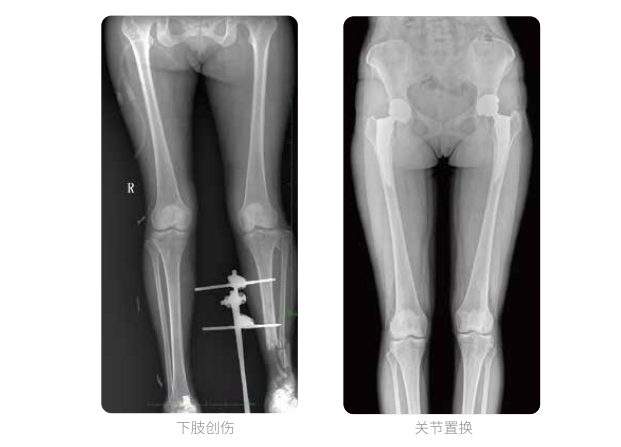

雙下肢臨床影像

普愛醫(yī)療動(dòng)態(tài)數(shù)字化X線攝影(動(dòng)態(tài)DR)可以整體顯示雙髖至雙踝關(guān)節(jié),直觀的展示因關(guān)節(jié)軟骨磨損和軟組織不平衡所造成的畸形及力線異常,全面對(duì)比了解雙下肢的病變情況。對(duì)于下肢矯正和人工關(guān)節(jié)置換術(shù)的術(shù)前計(jì)劃,術(shù)后觀察有著重要的臨床意義。